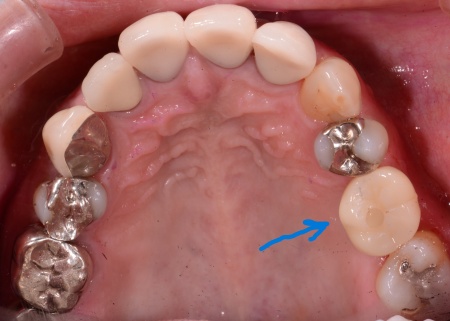

経過観察後、インプラント体と顎の骨が結合したタイミングで、インプラント体の上に装着するセラミックの被せ物を作製しました。

最後に、完成した被せ物を装着して、見た目や噛み合わせに問題がないことを確認し、治療を終了しています。

画像をクリックすると拡大・詳細コメントを確認いただけます